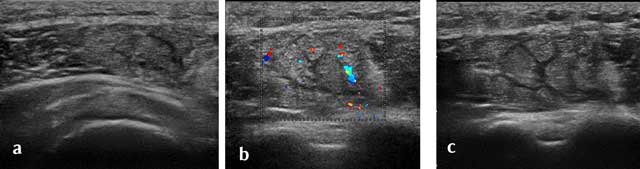

Figure 18

Axial view of a recent traumatic extrinsic lesion of the medium chief of the deltoid with hyperhemia (a–c).